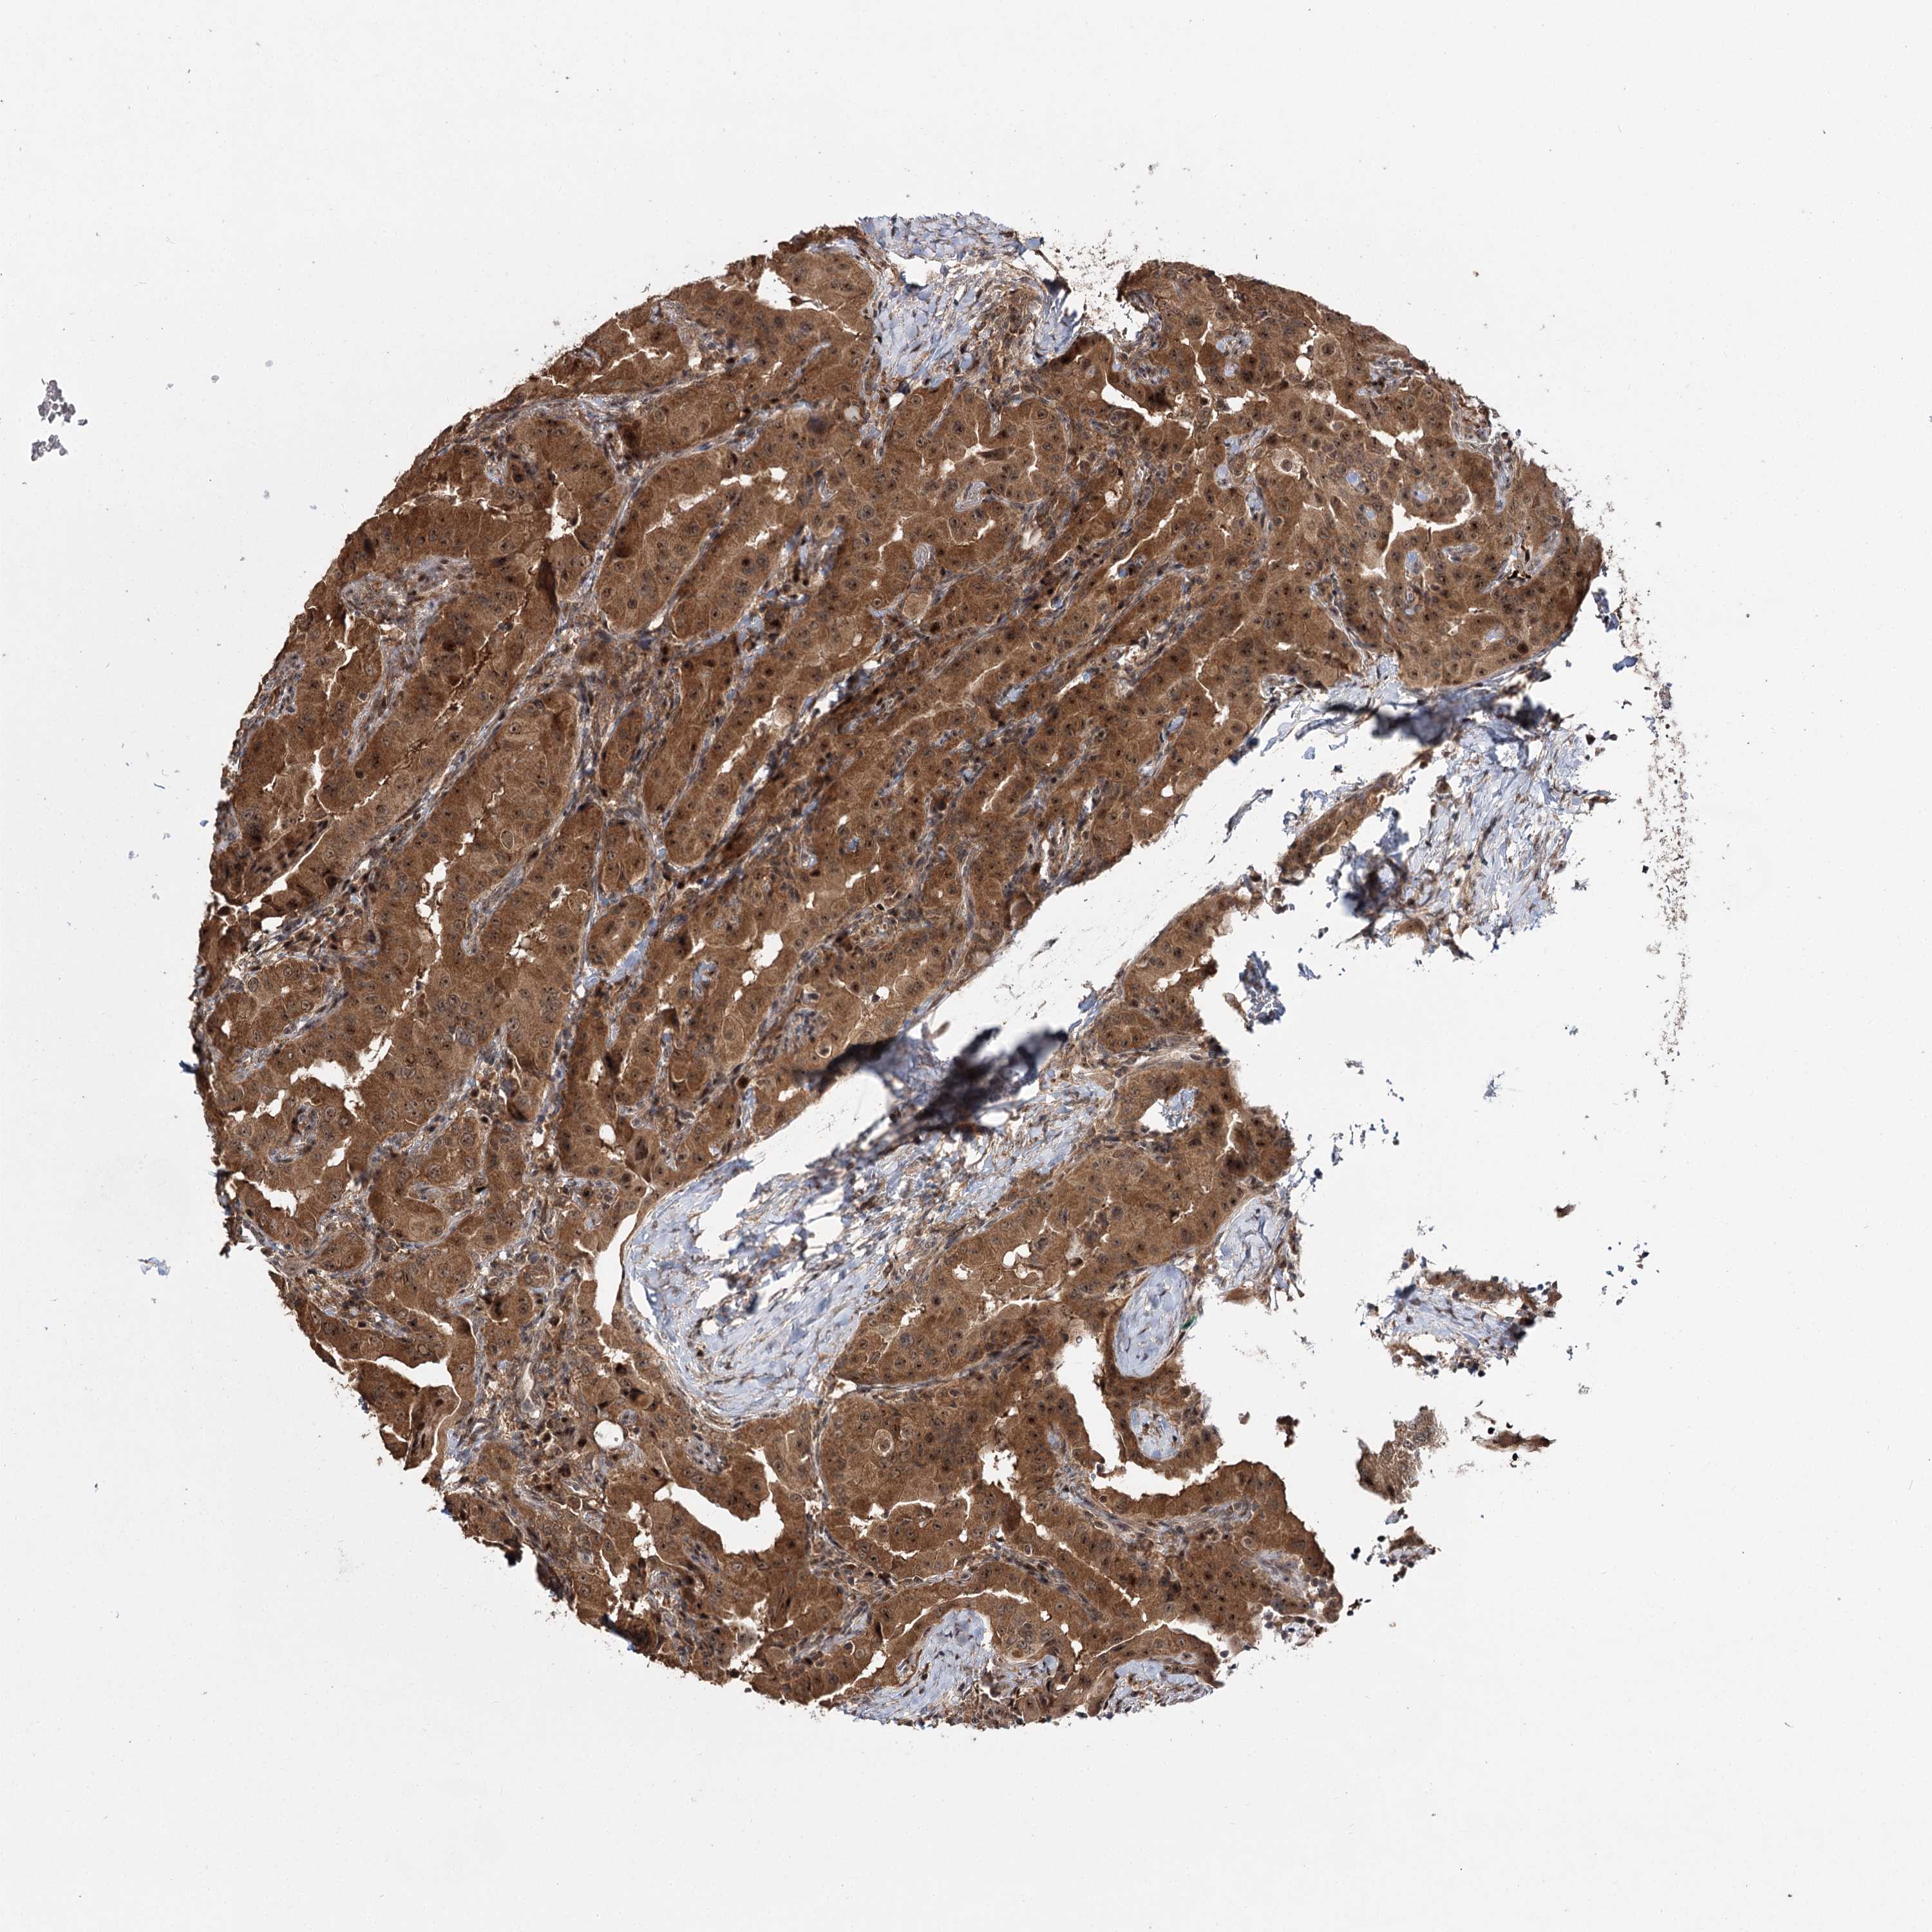

THYROID CANCER - Protein expressioni

A mouse-over function shows sample information and annotation data. Click on an image to view it in a full screen mode. Samples can be filtered based on level of antibody staining by selecting one or several of the following categories: high, medium, low and not detected. The assay and annotation is described here.

Note that samples used for immunohistochemistry by the Human Protein Atlas do not correspond to samples in the TCGA dataset.

Antibody stainingi

Antibody staining in the annotated cell types in the current human tissue is reported as not detected, low, medium, or high, based on conventional immunohistochemistry profiling in selected tissues. This score is based on the combination of the staining intensity and fraction of stained cells.

Each image is clickable and will lead to virtual microscopy that enables deeper exploration of all samples and also displays staining intensity scores, fraction scores and subcellular localization as well as patient and tissue information for each sample.

Antibody HPA021875

Antibody CAB037253

Staining

High

Medium

Low

Not detected

Intensity

Strong

Moderate

Weak

Negative

Quantity

>75%

75%-25%

<25%

None

Location

Nuclear

Cytoplasmic/membranous

Cytoplasmic/membranous,nuclear

Papillary adenocarcinoma, NOS

Follicular adenoma carcinoma, NOS